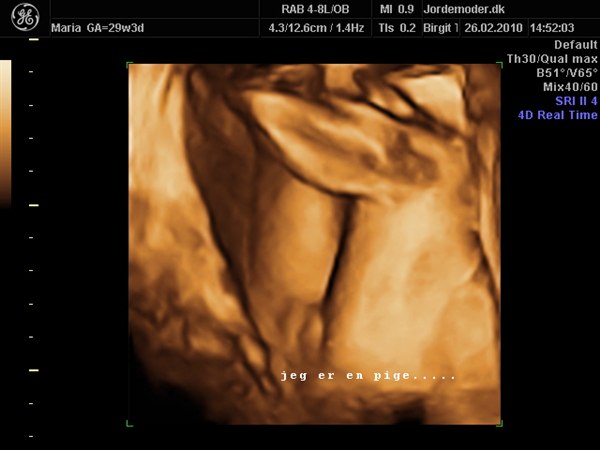

Jeg har et, men det er dog fra min 3d/4d scanning, så jeg er 29+3 mener jeg..

Det næste, der er hendes skamlæber lige over "også"..

Håber du kan se hvad det ligner..